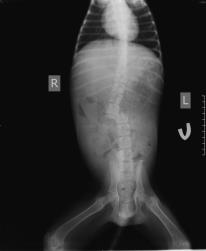

- Joshua’s X-rays 19 March